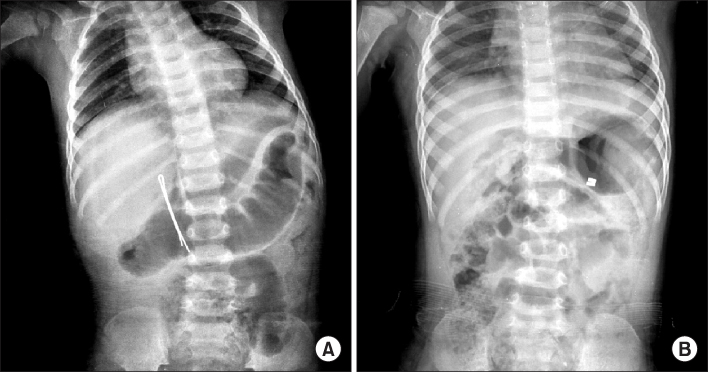

Fig. 3.

(A) Perforation of duodenal second portion by hair pin. (B) Perforation of gastric greater curvature and jejunum by two magnets.

Fig. 3. (A) Perforation of duodenal second portion by hair pin. (B) Perforation of gastric greater curvature and jejunum by two magnets.